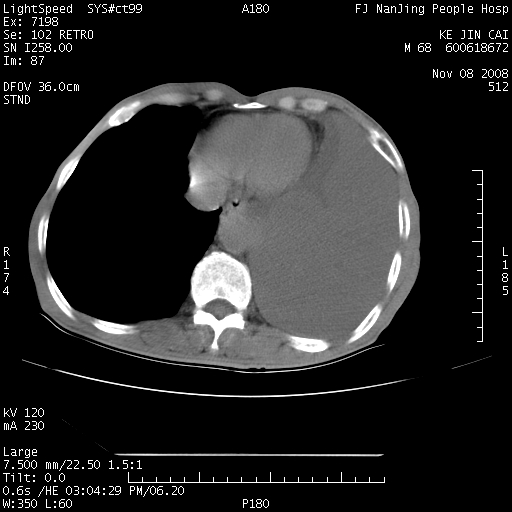

是个很有看头的病例,咋人气那么不旺?没多少人兴趣呢?这个病例几大怪:1   恶性肿瘤侵犯心肌左房怪,心肌一般不会被恶性肿瘤侵犯吧?2   左下肺均匀实变怪,内无含气,有别一般不张实变,含气肺泡完全为液体取代,而非一般不张实变的肺萎陷,冷不丁还以为是肿大的脾脏3   肿瘤本身怪,像tb肺不张4   这么有看头的病例没人气怪。呵呵。

左肺恶性肿瘤侵犯肺动脉,左心房内瘤栓,胸膜转移。

左肺恶性肿瘤侵犯肺动脉,左心房内瘤栓,胸膜转移,少见,学习了。